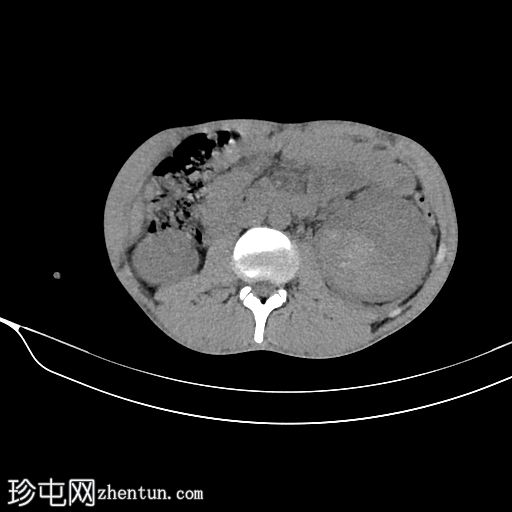

轴位增强扫描(门静脉期)

左肾包膜下(毗邻肾后包膜)可见一相对高密度、无强化的积液(平扫时HU=70),包绕左肾。

左肾下极可见肾实质不连续(>1 cm,未累及集合系统),提示

肾脏

撕裂伤部位。

左肾受巨大血肿压迫;但可见肾实质强化正常,造影剂排泄至集合系统。未见造影剂外渗。

III级肾损伤的特征(撕裂伤>1厘米,未累及集合系统,血肿局限于肾周筋膜内)